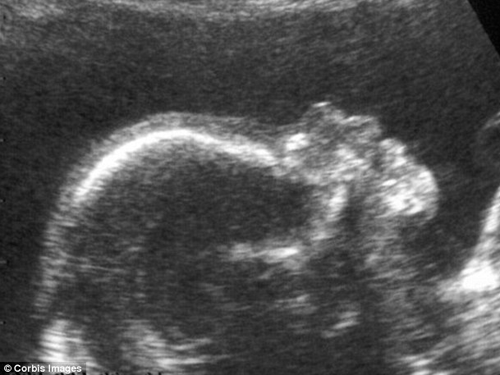

| Y tá đang kiểm tra tình trạng bào thai cho cô Yang Huiqing trước khi cô được sinh mổ tại bệnh viện Ruijin, Thượng Hải. Yang và chồng cô là Chen Yiming, cả hai đều sinh ra trong quy định có một con duy nhất. |